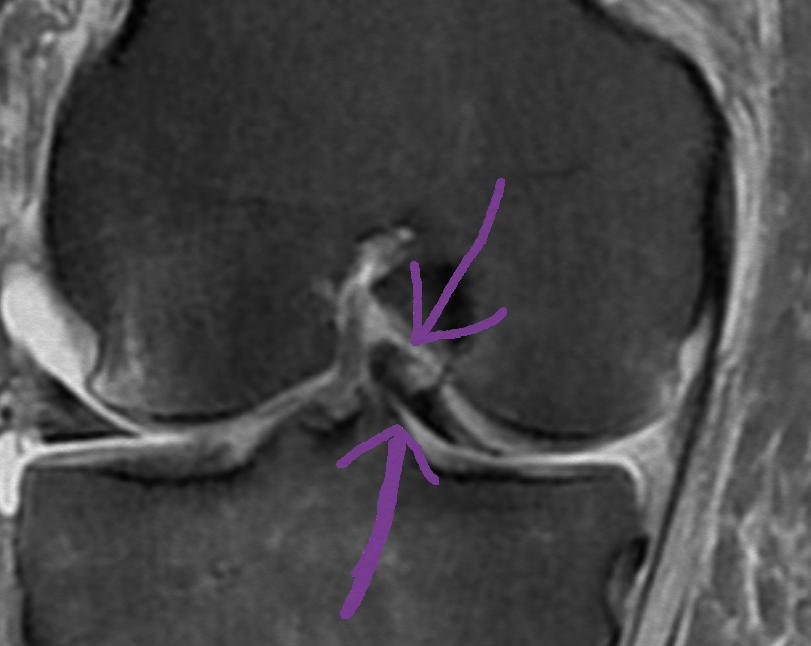

Web¿Qué síntomas produce una rotura de menisco? En el momento de la rotura el paciente siente un dolor vivo y con frecuencia un chasquido. En las horas siguientes la rodilla. WebLas roturas del menisco con asa de cubo comprenden casi el 10% de todas las roturas meniscales, afectando generalmente a población joven masculina. El desplazamiento. WebDiagnóstico. Un menisco desgarrado a menudo puede identificarse durante un examen físico. Es posible que el médico te coloque la rodilla y la pierna en diferentes. WebNo soy una persona que practique deporte a nivel élite, pero si deseo jugar de manera regular. PARTE MÉDICO: -Diagnóstico: rotura en ASA de cubo menisco medial.. WebHabitualmente basta con la exploración del médico para efectuar el diagnóstico, pudiendo confirmarlo una ecografía. Si la rotura es parcial el tratamiento es. WebUna rotura de menisco grave que afecta a la rodilla es la rotura en asa de cubo. Se trata de una lesión que provoca hinchazón y dolor y que puede dificultar. WebRotura en asa de cubo menisco interno se precisa cirugía urgente ya que provoca bloqueo de extensión de la rodilla. Realizamos sutura artroscópica con dos puntos fuera-dentro. WebHace 5 meses tuve una lesión que me provocó una rotura del menisco en asa de cubo. Altualmente me encuentro a la espera de visita con cirujano para programar operación..

WebRotura en asa de cubo menisco interno se precisa cirugía urgente ya que provoca bloqueo de extensión de la rodilla. Realizamos sutura artroscópica con dos puntos fuera-dentro. WebHace 5 meses tuve una lesión que me provocó una rotura del menisco en asa de cubo. Altualmente me encuentro a la espera de visita con cirujano para programar operación.. WebReparación artroscópica de una rotura en “asa de cubo” de menisco interno Microfracturas en escotadura intercondílea y aspirado de médula ósea para mejorar.